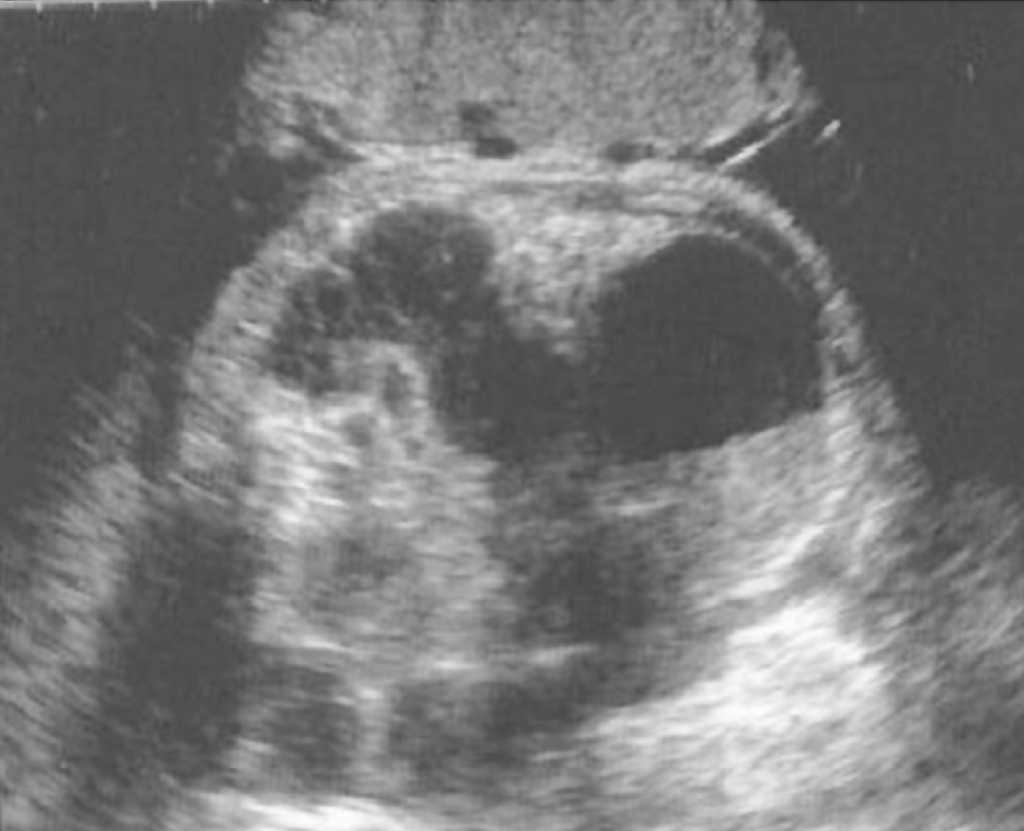

En un primer estudio ecográfico, practicado en la semana 32 + 2, destaca un circunferencia abdominal fetal (CAF) mayor al percentil 95 y un polihidramnios con índice de líquido amniótico (ILA) de 23. En el hemiabdomen inferior se visualiza una tumoración redondeada de aspecto quístico, desde la vejiga al borde hepático, de 59 x 48 x 46 mm de diámetro, con nivel líquido-sólido, compatible con quiste ovárico fetal, con parte sólida avascular (figs. 1 y 2). Las asas intestinales distales se encontraban dilatadas, con peristaltismo y rechazadas en hemiabdomen izquierdo probablemente por compresión extrínseca (fig. 3). No se visualiza líquido libre ni calcificaciones. El resto de la exploración ecográfica se encontraba dentro de la normalidad.

Figura 2.Corte sagital del abdomen fetal con asas intestinales dilatadas con contenido en su interior.